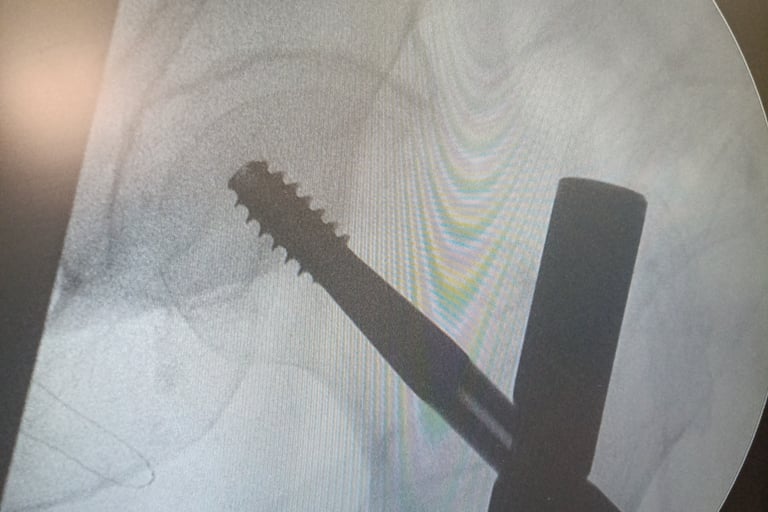

- Tratamento cirúrgico de fraturas ( transtrocanteriana, subtrocanteriana, diafisária de fêmur, acetábulo )